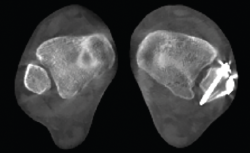

Figura 3. Inestabilidad franca de la columna medial en pie plano.

- Pie plano valgo del adulto. Permite la valoración de la articulación subtalar, el valgo del retropié y la inestabilidad de la columna medial (Figuras 2 y 3).

- Inestabilidad de la columna medial o inestabilidad tarsometatarsiana. Valoración y estudio de la columna medial en carga (Figuras 5 y 6).